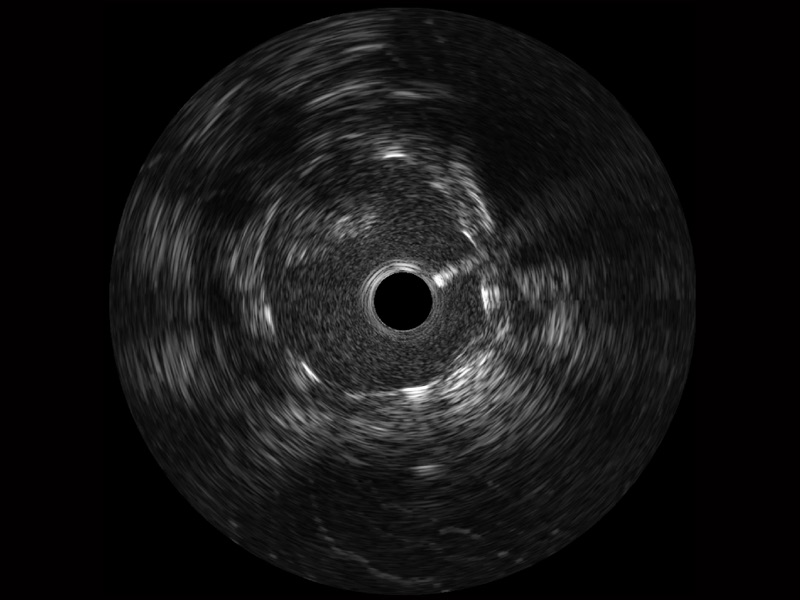

传统IVUS图像

对比传统IVUS导管成像,乐玩lewin国际宽频IVUS图像的近场支架梁显影更细腻,远场中膜外血管仍清晰可辨,兼顾远中近,兼顾分辨力与穿透深度